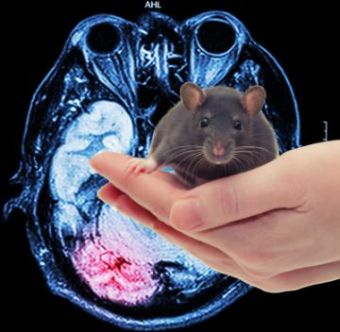

“蓝色大脑计划”是瑞士的一项研究倡议,最终目的是通过超级计算机对人脑进行数字重建。目前为止,在重建和模拟大鼠大脑皮层电路的过程中,已在约31000个神经元(神经细胞)之间进行了约 800 万次连接。这远远低于人脑中约 1000 亿个神经元,仅代表了比人脑小得多的大鼠大脑的一小部分,大鼠大脑共有约 1300 万个神经元。

该研究的作者(Reimann等人)猜测,当大脑处理一个刺激时,与该刺激相关的活动将把通过突触相连的神经元组合在一起,形成“功能团”(紧密相连的神经元群)和“空腔”(这些神经元群之间的“空白区”),然后“按照模式化的顺序向最高复杂度”

行进。首席研究员亨利·马克拉 (Henry Markram)认为:“即使在大脑的一个小点中,也有数千万个此类物体,起码有7个维度。在一些网络中,甚至发现有高达 11 个维度的结构。”

这些不是空间时间维度,而是数学维度概念。可以将其想像为一个几何物体,由功能团中的所有神经元相互连接而构成。功能团中的神经元越多,该物体的维度就越高。

如果这种脑模型是准确的,那么,哪怕模拟大脑的一小部分,也能看出大脑处理信息时的功能复杂性已达到令人眼花缭乱的水平。更让人困惑的是这种复杂度如何在进化的过程中——在自然选择对随机突变的作用下被写入我们的基因。